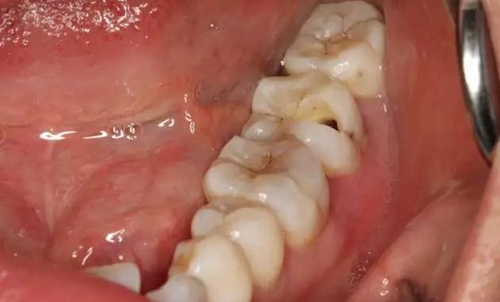

圖1.患者自述右側下后牙牙齦紅腫,咀嚼不適。術前口內(nèi)像:37頰側牙齦紅腫

10.jpg